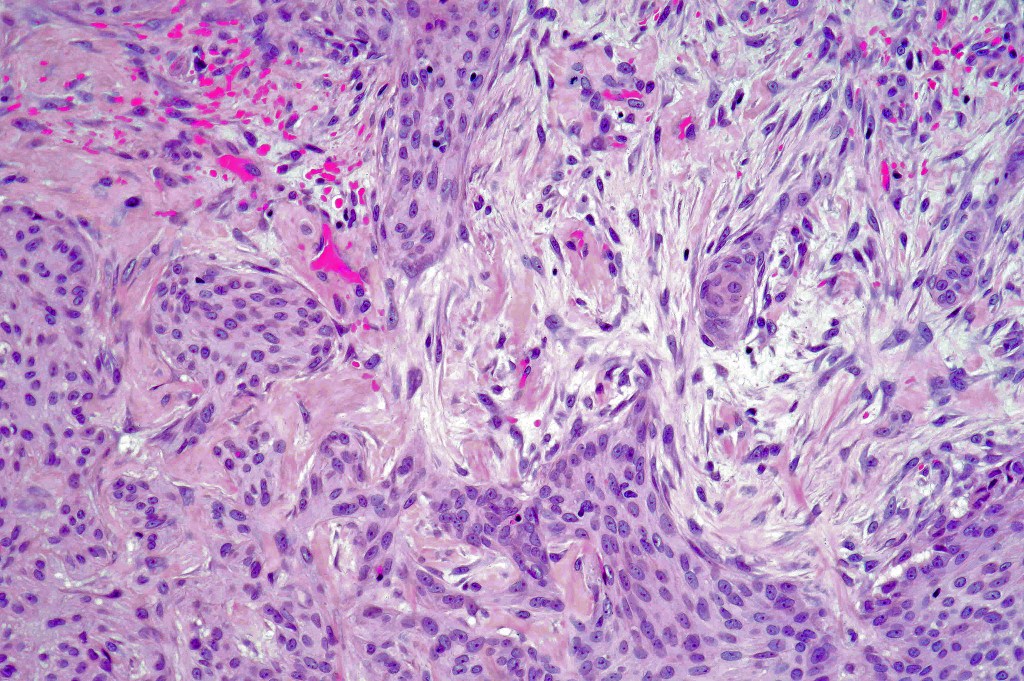

Histological features

•Typical trichilemmoma surrounding a densely, hyalinized collagenous region containing narrow epithelial strands sometimes mimicking a carcinoma

•The stroma contains glycogen & acid mucopolysaccharides & is DPAS+ve

•Stromal component is rich in type 1 collagen

The diagnosis of both these tumors is nearly always readily apparent. The desmoplasia can result in suspicion of malignancy by the unwary. Trichilemmoma can be distinguished from poroma by the hyalinized thick basement membrane and absence of ducts. Desmoplastic trichilemmoma is distinguished from squamous carcinoma by the presence of typical trichilemmoma at the periphery and from trichilemmal carcinoma by the absence of pleomorphism & significant mitotic activity. Trichilemmal carcinoma does not show a pre-existent trichilemmoma. CD34 expression excludes squamous carcinoma